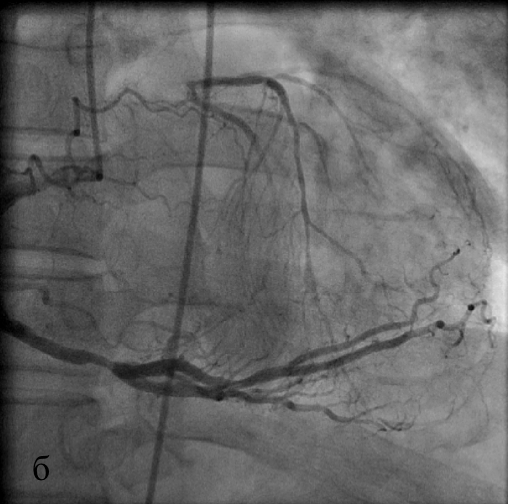

На исходных коронарограммах выявляются тотальная окклюзия ствола ЛКА (а), система ЛКА заполняется по межсистемным коллатералям из бассейна ПКА (б).